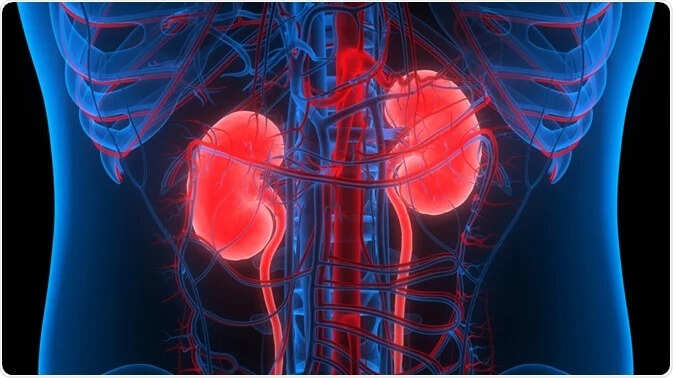

உங்க சிறுநீரகம் சிறப்பாக செயல்படவில்லை என்பதை காமிக்கும் அறிகுறிகள்

உடலின் கழிவு தொழிற்சாலை என்று அழைக்கப்படும் கிட்னியை பாதுகாப்பது மிகவும் முக்கியம் .வீட்டுக்குக் கழிவறை எப்படி முக்கியமோ அதுமாதிரி நம் உடலுக்குச் சிறுநீரகம் முக்கியம்.

கிட்னி ஆபத்தில் உள்ளது என்பதை காமிக்கும் அறி குறிகள்